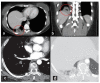

Pulmonary infarction (PI) is a possible consequence of pulmonary embolism (PE). The real incidence of PI could be underestimated considering only non-fatal PE presentation. However, following postmortem examination, the prevalence of PI is considerably higher. This evidence suggests the necessity of proper diagnostic protocol for identifying PI. Unfortunately, PI diagnosis can sometimes be challenging, due to the overlapping of symptoms with other diseases. Nowadays, the diagnosis is mainly based on radiological evaluation, although the combination with emerging imaging techniques such as ultrasound and nuclear scanning might improve the diagnostic algorithm for PI. This review aims to summarize the available data on the prevalence of PI, the main predisposing factors for the development of PI among patients with PE, to resume the possible diagnostic tools, and finally the clinical and prognostic implications.